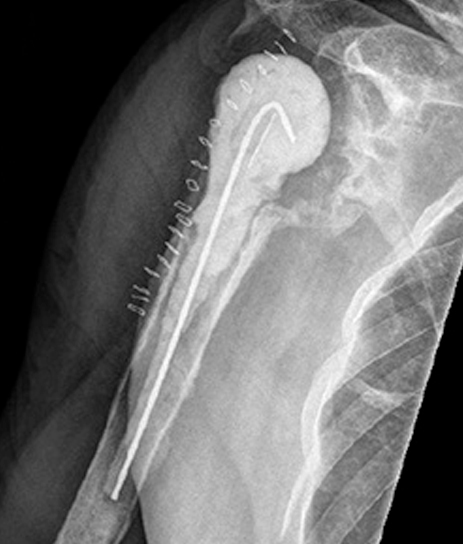

For fracture and revision treatment

The system offers a set of modular Proximal Bodies in several sizes and heights to be paired with a broad range of Modular Stems, available in different diameters and lengths as well as different surface and coating options for cemented and cementless fixation.

The Proximal Bodies’ spiked surface, together with m-l and a-p holes for suture fixation, allow for stable and physiologic tuberosities reattachment. The modular concept of the fracture components supports the surgeon in achieving adequate joint restoration even in cases with poor anatomical landmarks.1